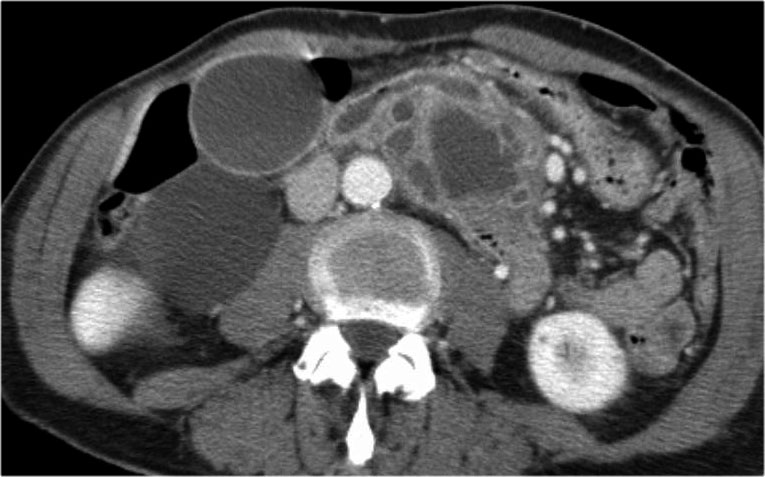

Hình ảnh CT của bệnh nhân nữ 32 tuổi với triệu chứng đau vùng thượng vị trái lan ra sau lưng.

Ghi nhận một nang lớn ở đuôi tụy có vôi hóa ngoại vi.

Có vách ngăn mờ nhạt như thấy trên hình bên trái và thành nang dày.

Có thể cần phóng to hình ảnh để quan sát rõ vách ngăn.

Có thể đưa ra chẩn đoán đặc hiệu là MCN.